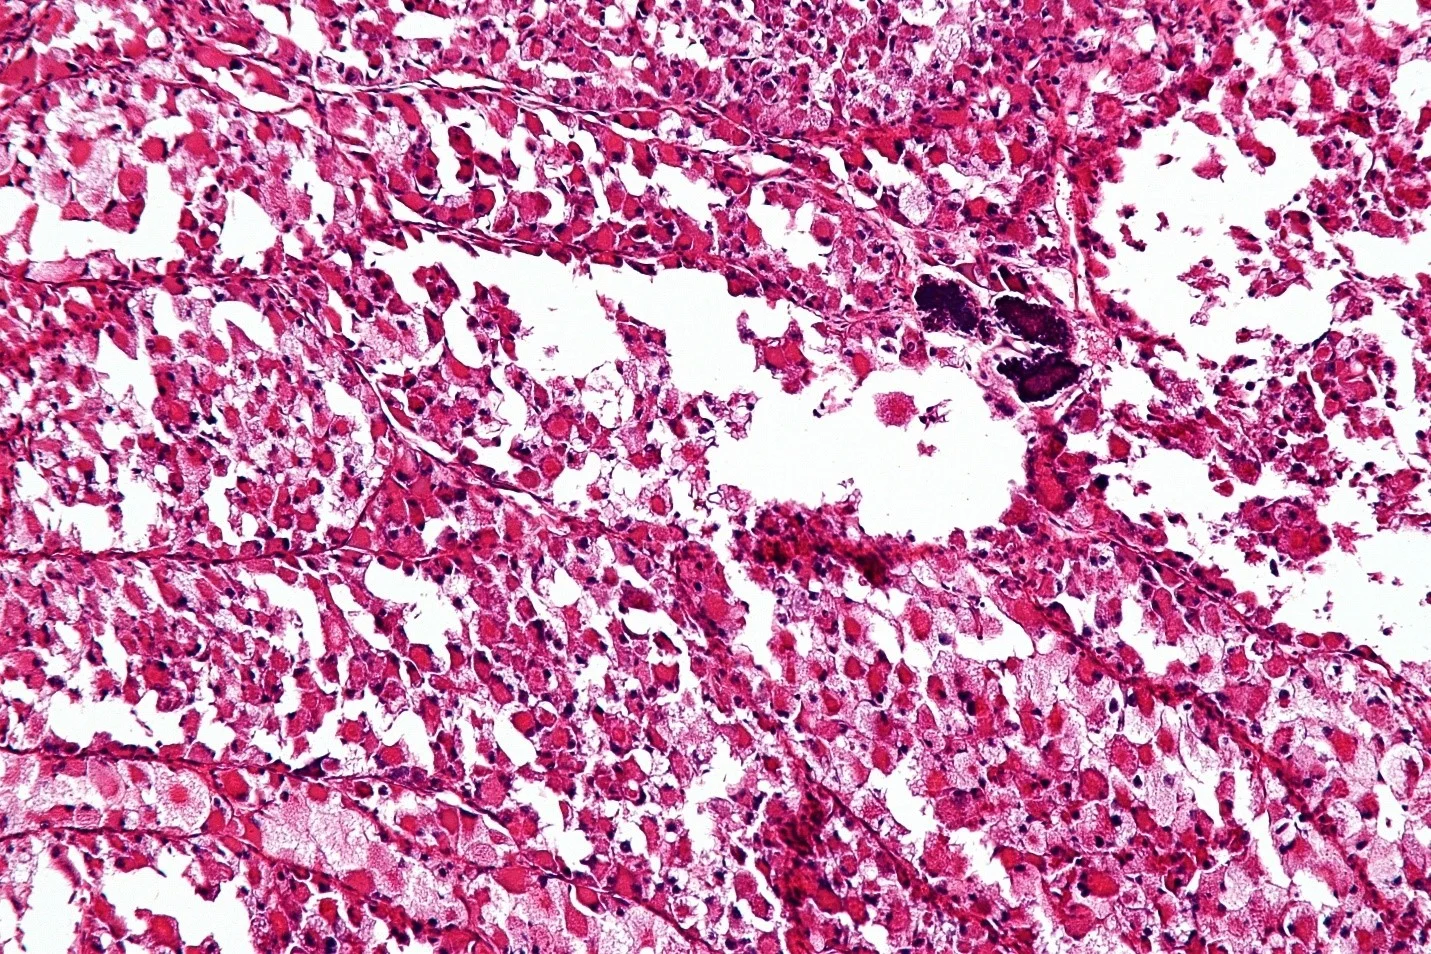

- آنژیوسارکوم (Angiosarcoma) میتواند در عروق خونی (همانژیوسارکوم یا hemangiosarcomas) یا در عروق لنفاوی (لنفانژیوسارکوم یا lymphangiosarcomas) شروع شود. این تومورها گاهی در قسمتی از بدن که تحت درمان با اشعه قرار گرفته است، شروع میشوند. گاهی اوقات آنژیوسارکوم در پستان پس از پرتو درمانی و در اندامهای مبتلا به ادم لنفاوی دیده میشود.